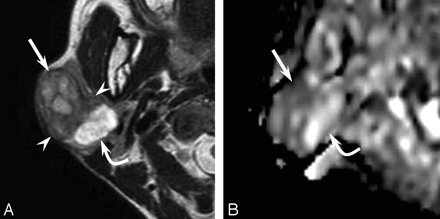

A 48-year-old woman felt a slowly enlarging right parotid gland for 5 years. The parotid mass was painless without facial nerve paralysis. T2-weighted images exhibited the 35 × 25 mm mass in a well-demarcated area of heterogeneous intensity (Fig 1A). The lateral component showed mild high intensity; the intermediate component, low intensity; and the medial component, extremely high intensity on T2-weighted images. Diffusion-weighted and apparent diffusion coefficient (ADC) mapping images revealed the lateral component as hypercellular and the intermediate and medial components as hypocellular (Fig 1B). A histopathologic examination of the surgical specimen documented pleomorphic adenoma and an epithelial malignancy, like myoepithelial carcinoma. The lateral component was documented as carcinoma; the intermediate component, as pleomorphic adenoma with marked fibrosis; and the medial component, as pleomorphic adenoma with a marked chondroid matrix.

A 48-year-old woman with a carcinoma ex pleomorphic adenoma (case 1). A, Axial T2-weighted image (fast spin-echo: TR/TE, 4102/90) shows a well-demarcated mass with heterogeneous intensity of the right parotid gland. The lateral component shows mild high intensity (arrow), the intermediate component shows low intensity (arrowhead), and the medial component shows extremely high intensity (curved arrow). B, ADC mapping image shows the lateral component of hypercellularity with carcinoma (arrow) and the intermediate and medial component of hypocellularity with pleomorphic adenoma (curved arrow).